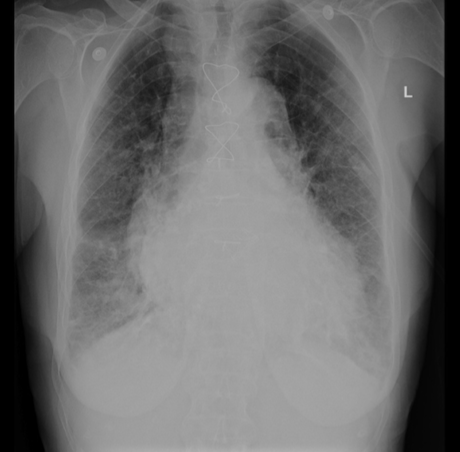

75yo male with CHF presents with dyspnoea. Crackles are heard at the lung bases on examination

Pulmonary oedema